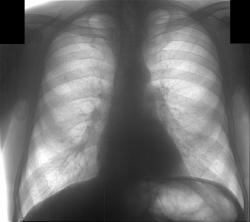

beg.jpg

Первое исследование - цифровая флюорография, зарегестрировано как профилактическое (возможно ошибочно). Заключение - спайка в лев косто-диафрагмалном синусе, других изм. не выявлено.

Иконка изображения beg.jpg212.74 КБ

Достал и прикрепил первичную флюорограмму (beg), сделана за 10 дней до нижеследующих. Мне кажется на ней угадывается тень за сердцем, на уровне головки 9 р.?